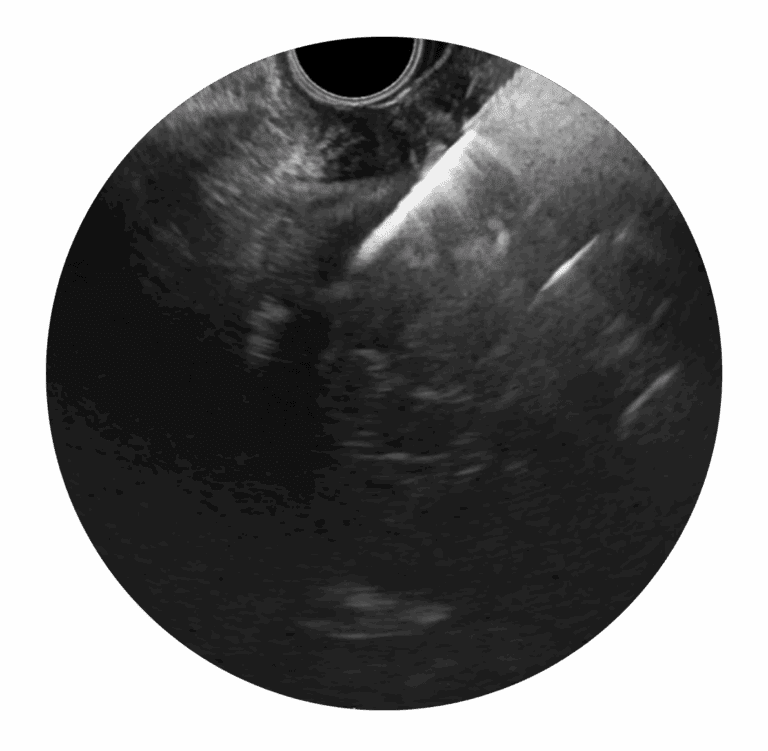

Unlike conventional manual needle instruments, EndoDrill® features a motorized, rotating drill-tip cylinder. This design enables deep, precise tissue sampling. One or more solid core biopsies are extracted, providing the tissue architecture required for complete histological diagnosis, staging, and genetic analysis.